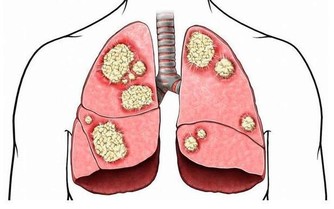

|  老年人的眼睛健康問題已經逐漸成為困擾60歲以上老年人的主要問題之一。據權威調查顯示,60歲以上老人眼睛存在的健康方面的問題的比例在95%,老年人其中大多數眼睛疾病和問題可以在早期得到重視的情況下可以避免,但是大多數老人對於自己的眼睛問題不太在意,往往造成日後的嚴重後果。注意老人眼健康,從防以下“十害”開始。營養不良 在營養中與眼關係最大的是維生素A、B族維生素和維生素C。維生素A會影響視網膜的夜間感光效應,維生素A缺乏會引發“夜盲症”、眼乾燥症與角膜軟化。視網膜就是視神經的末梢,所以最需要營養神經的B族維生素。維生素B1缺乏,易發生眼乾燥症、視神經炎;維生素B1缺乏,常會導致視神經炎、瞼緣炎、結膜炎等。維生素C在人眼中的含量高出血液30倍,維生素C缺乏,會引起眼瞼、前房、玻璃體、視網膜等部位出血,還可導致白內障。 白內障 白內障是指晶狀體因各種原因發生渾濁,由透明變成不透明,阻礙了光線進入眼內所致。主要症狀是無感覺的進行性視力減退和視物模糊,若逐漸加重會導致失明。注意預防代謝性和並發性白內障。如患糖尿病就易誘發白內障,應注意預防。 糖尿病 如果患了糖尿病,而病情又沒有得到及時控制,常會並發糖尿病眼病。該病一般早期常無明顯眼部自覺症狀,隨著病變發展,可引起不同程度的視力下降、看物變形、眼前黑影飄動、視野缺損(看見的範圍減小)、眼部脹痛等症狀,最終可發展至失明,是重要的致盲眼病之一。由於其症狀多數是無痛性發展的,容易被忽視。所以,糖尿病患者若雙眼有上述異常表現,必須提高警惕。 黃斑變性 是由於黃斑區的衰老變性引起的。大多數研究認為它與視網膜色素上皮的代謝功能衰退有關。一般認為與遺傳、慢性光損害、營養不良、心血管系統和呼吸系統疾病以及環境因素等有關。主要症狀是無痛性視力下降,所見物體變形,自覺眼前有固定的黑影遮擋(總感覺所見物體中央有灰色陰影)。隨著病程進展,嚴重者可失明。現代研究認為,黃斑區富含葉黃素,常吃富含葉黃素的食品如枸杞子、玉米等,或服中成藥明目地黃丸(杞菊地黃丸)有很好的預防作用。  動脈硬化、高血壓

引起的眼部變化主要是眼底血管的改變,表現為眼底微血管變細、扭曲、滲出,甚至血管破裂、出血,會造成患者視力下降或突發性看不見東西。主要防治辦法就是控制血壓、血脂。所以,中老年人的飲食,應貫徹低脂、低鹽、低糖的原則,重視對動脈硬化和高血壓的防治。檢查身體時不要忘記檢查眼底。 外傷感染 雙眼角膜因為在眼球表面,所以最怕外傷和病毒、細菌感染。人們常說“眼睛裡揉不得沙子”,說的就是角膜容不得半點灰塵等異物。特別是人到老年,眼淚減少,角膜乾燥,角膜更易受到損傷。所以,平時要加強對角膜的保健和防護,避免灰塵異物損傷,避免強光照射,重視衛生,不要用臟手亂揉眼睛,平時宜少吃辛辣刺激性食品,少飲酒。此外,防止眼外傷、及時補充飲水等,對保護雙眼的健康都很重要。 屈光不正 在靜止狀態下,平行光線經眼屈光系統的折射後聚焦於視網膜上,這便是正視眼。若平行光線經眼屈光系統的折射後不能聚焦於視網膜上,這是非正視眼,稱為“屈光不正”。屈光不正包括近視、遠視及散光。特別是患高度近視而沒有得到及時矯正,最易導致“視網膜脫離”(就是視網膜感光層與其下層組織之間的分離),是引發失明的重要原因。 顱內壓增高 無論是顱腦外傷、炎症或腫瘤,只要引起顱內壓力增高,就會影響眼靜脈的回流,出現視乳頭水腫,損害視神經,嚴重者可導致失明。顱內腫瘤還會直接壓迫視神經或損壞視中樞而造成視野缺損或導致不同程度的非眼病性致盲。所以,一定要加強預防顱腦外傷,重視對腦部炎症和腫瘤的防治。 青光眼 眼壓是眼球內容物(房水、晶狀體和玻璃體)對眼球壁施加的壓力。一旦房水循環阻塞、眼壓升高,就會患青光眼。此病若沒有得到及時診斷和治療,患者可能會在數天,甚至數小時內失明。急性閉角型青光眼可雙眼先後發病,也可同時發病。世界上約有五分之一的眼盲為青光眼所致。平時體檢不要忘了測眼壓,一旦發現眼壓升高或發現青光眼的症狀,一定要立即求診,唯有及時手術才能保住視力。  老花眼